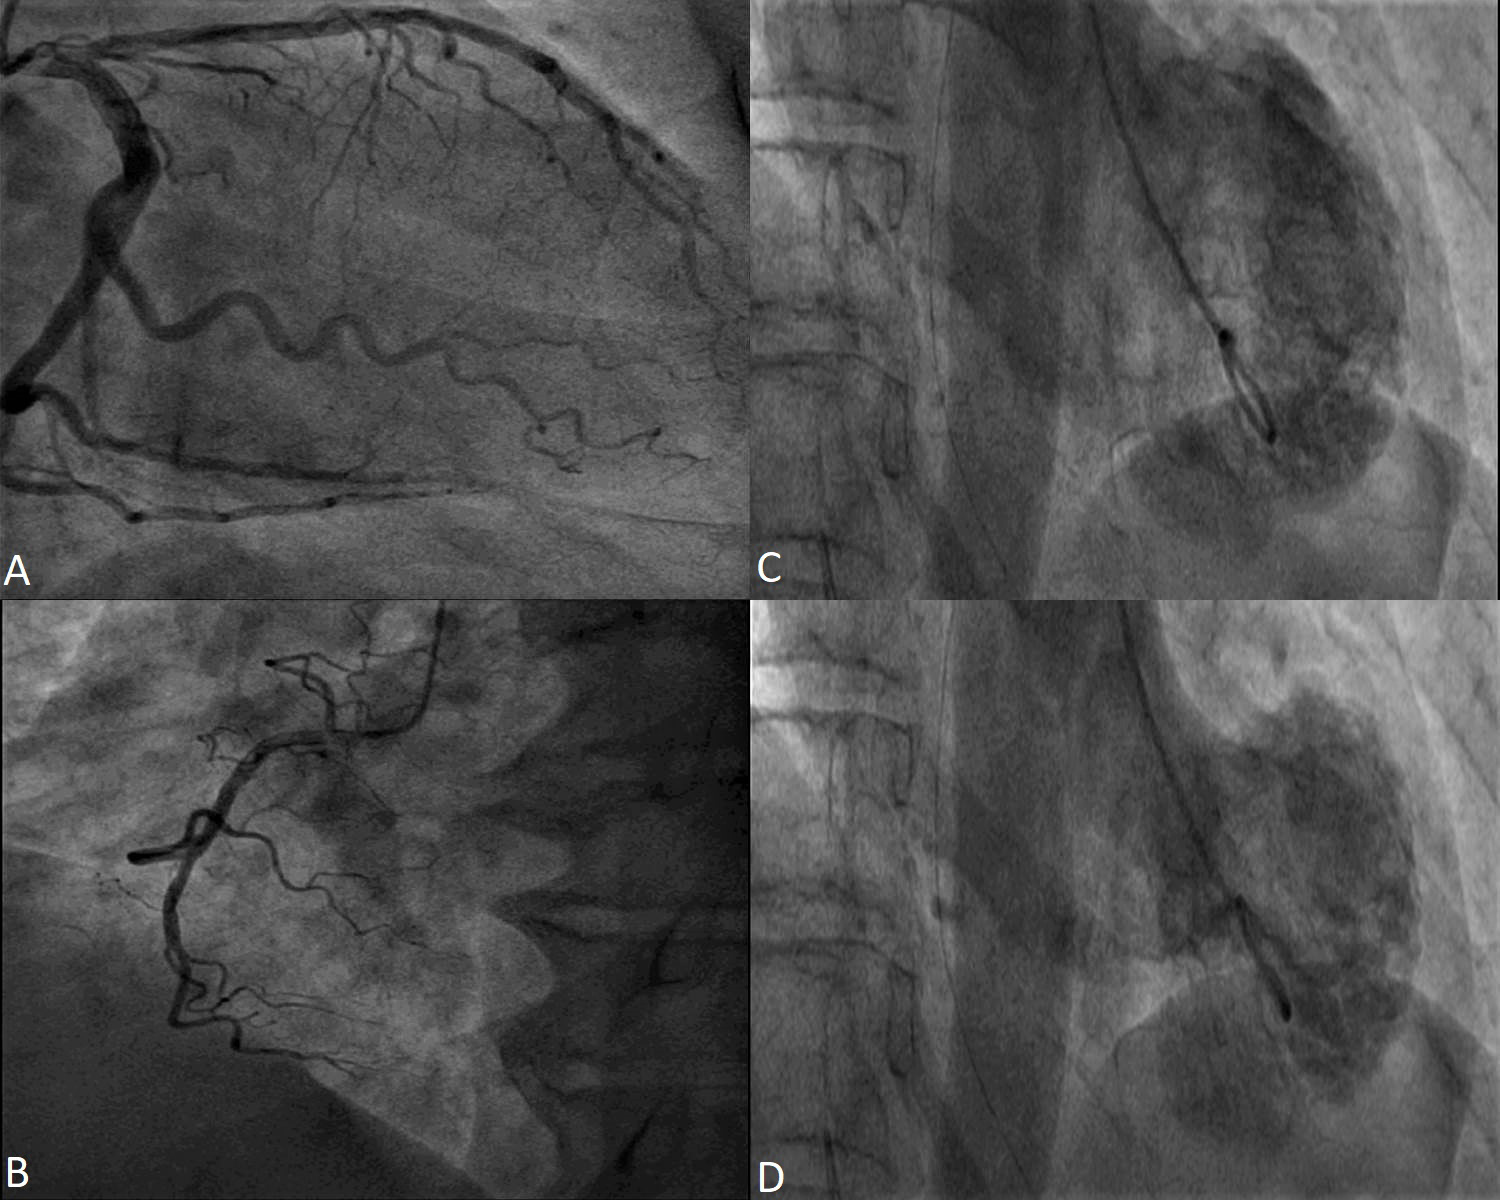

Since the most frequent clinical presentation of a TS case is that of an acute coronary syndrome with ST segment elevation, the main investigation is coronary angiography in order to exclude a type 1 myocardial infarction [23, 24]. Coronary arteries need to be carefully assessed, in several angiographic views. Usually, patients with TS have non obstructive epicardial coronary arteries but coronary disease unrelated to the motion anomaly of the LV may be present. However, coronary artery disease is not an exclusion criteria [25]. The main reason is that the regional wall motion abnormalities (RWMA) extend beyond the vascularization of a single coronary artery [26]. Even if the patient has coronary artery disease, it is not an exclusion criteria if the depending myocardial territory is not concordant with the wall motion abnormalities [27, 28]. When coronary artery disease is found, orthogonal angiographic views of the artery and LV ventriculography help in observing the mismatch between the coronary stenosis and the wall motion abnormality. The “apical nipple sign” was described on ventriculography images: a small zone, right at the LV apex, with preserved contractility, found in approximately 30% of TS patients with apical pattern. This sign was not described in patients with acute anterior myocardial infarction and may help in differentiating the two conditions [29].

Most of the time, TS diagnosis is associated with angiographically normal or non-obstructive coronary arteries [30] (Fig. 1). In patients diagnosed with TS and coronary artery disease, intracoronary imaging techniques, like intravascular ultrasound and optical coherence tomography, revealed that coronary plaques had no sign of thrombosis, erosion or dissection [31, 32, 33, 34].

Fig. 1.

Fig. 1.Coronary angiography in a 53 year-old female patient with Takotsubo Syndrome. Non-obstructive epicardial coronary arteries - images (A) and (B). Ventriculography showing apical akinesia and basal hyperkinesia - images (C) and (D).